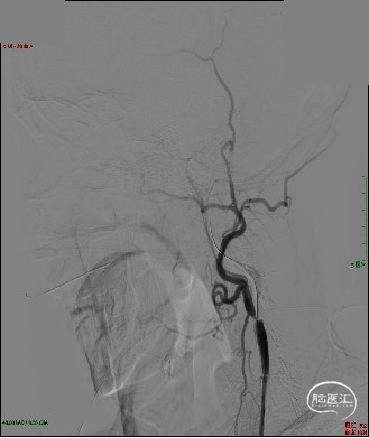

急诊DSA:LICA闭塞,LICA起始部次全闭塞。

急诊DSA:微导管于LICA-C2段造影见血栓近端所在,明确患者为LICA起始段次全闭塞合并远端栓塞的串联病变。

首先处理起始段狭窄-使用球囊(2×15mm、3×15mm、5×20mm)分3次逐渐扩张颈内动脉起始段。

SWIM技术取栓:半松球囊状态下Neuron Max 6F长鞘顺势送至C2段建立通路。

ACE 60再灌注导管送至血栓近端,微导丝、微导管穿过血栓至LMCA,6×30mm 取栓支架到位并释放。

双重负压抽吸下回撤取栓支架,造影见mTICI 3级再通。

保留微导丝,长鞘撤回颈总动脉,将远端保护装置放于岩段,置入7×40mm颈动脉支架。

支架释放,取栓支架及ACE 60内可见多量血栓。